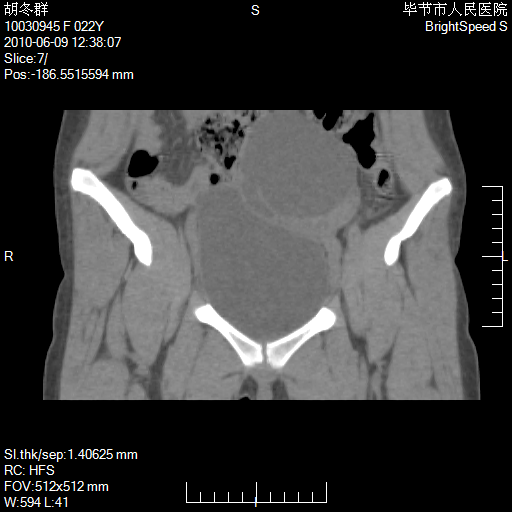

患者23岁,发现腹部包块3月。

左侧卵巢囊腺瘤或囊腺癌

盆腔内囊性占位性病变;考虑左侧卵巢囊腺瘤。

有分隔、壁薄,支持考虑左侧卵巢囊腺瘤。

左侧卵巢浆液性囊腺瘤。

有分隔、壁薄,支持考虑左侧卵巢囊腺瘤。排尿后,膀胱缩小,由于重力作用,肿块下移就到了膀胱位置,很好理解。